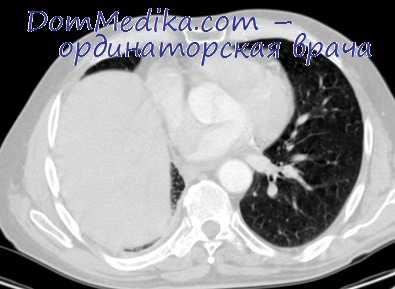

Верхняя лобэктомия справа

Легкое оттягивают кзади, диафрагмальный нерв берут на держалку. После двойного лигирования верхней легочной вены лигируют и пересекают V1 и V2 + V3. Затем выполняют перевязку и пересечение переднего ствола легочной артерии спереди, под непарную вену заводят держалку и отводят вену назад, после этого выполняют лигирование и пересечение A3 и А1 + А2. После лигирования и выделения легочной артерии берут на держалку бронх верхней доли легкого и завершают процедуру наложением шва. Выделяют область вокруг бронха, держалку проводят через нижнюю щель и отделяют клипсоап-пликатором. Важно отметить, что выделение бронха выполняют вместе с лимфодиссекцией.